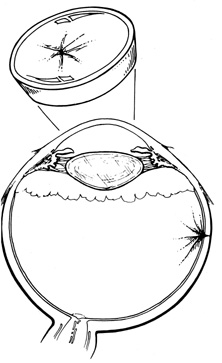

A helpful intraoperative sign to determine the adequacy of subretinal fluid drainage is to assess the contour of the retina in relation to the scleral buckle. If after drainage the retina follows the contour of the buckle, drainage is usually adequate even if there are residual subretinal fluid and retinal folds. However, if after drainage and elevation of the buckle the retina does not appear to follow the contour of the buckle or if the buckling effect is not visible beneath the retina, additional drainage usually is necessary (Fig. 33).

Fig. 33. A. Retinal tear elevated after drainage and placement of a scleral buckle. B. Retinal tear partially closed after drainage with the retina conforming to the shape of the buckle.